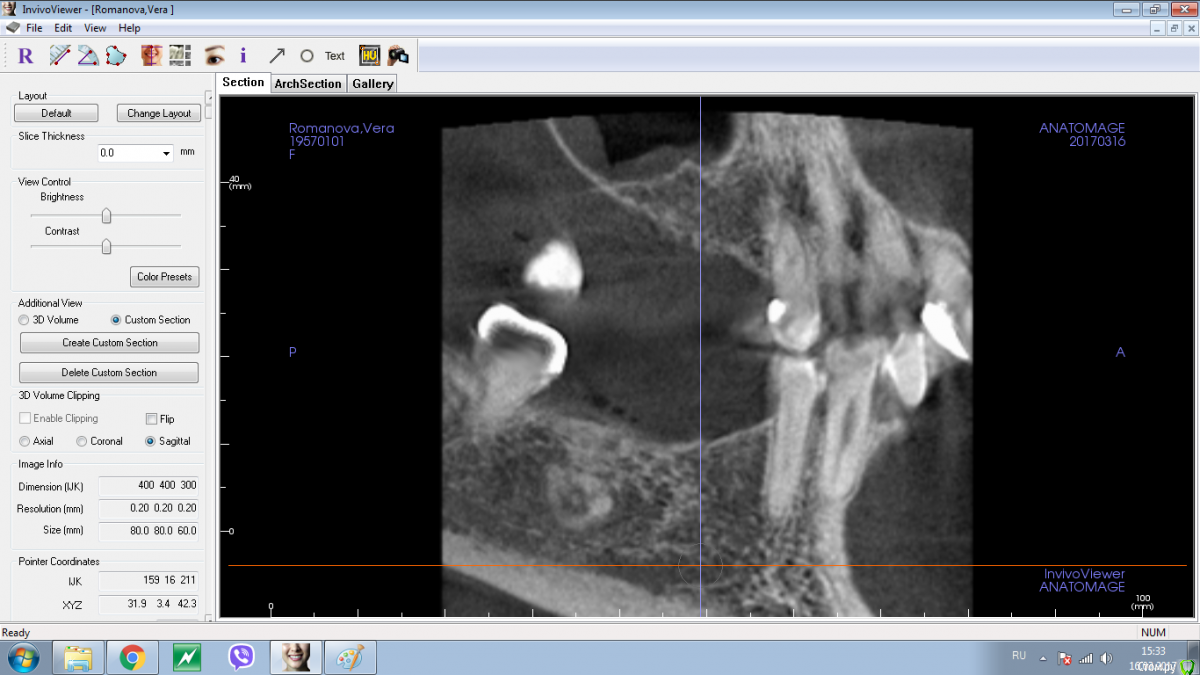

Shakirbura Опубликовано 18 марта, 2017 Поделиться Опубликовано 18 марта, 2017 Здравствуйте, коллеги!Пациентка обратилась по поводу протезирования на имплантатах. На снимке обнаружил вот такое образование. Раньше не встречал. Какими должны быть мои действия в таком случае?Спасибо! Ссылка на комментарий

Andrey Shiryaev Опубликовано 18 марта, 2017 Поделиться Опубликовано 18 марта, 2017 Похоже на остеому. Ссылка на комментарий

Kovalov Igor Опубликовано 19 марта, 2017 Поделиться Опубликовано 19 марта, 2017 Конденсирующая остеома.Покажите на Фейсбуке Рогацкину Дмитрию , читал что ставят прям в остеому Ссылка на комментарий

Карен Аванесов Опубликовано 19 марта, 2017 Поделиться Опубликовано 19 марта, 2017 Аккуратно убрать, поставить имплантат, при необходимости графт, если это остатки зуба будет видно. если нло на гистологию. Ссылка на комментарий